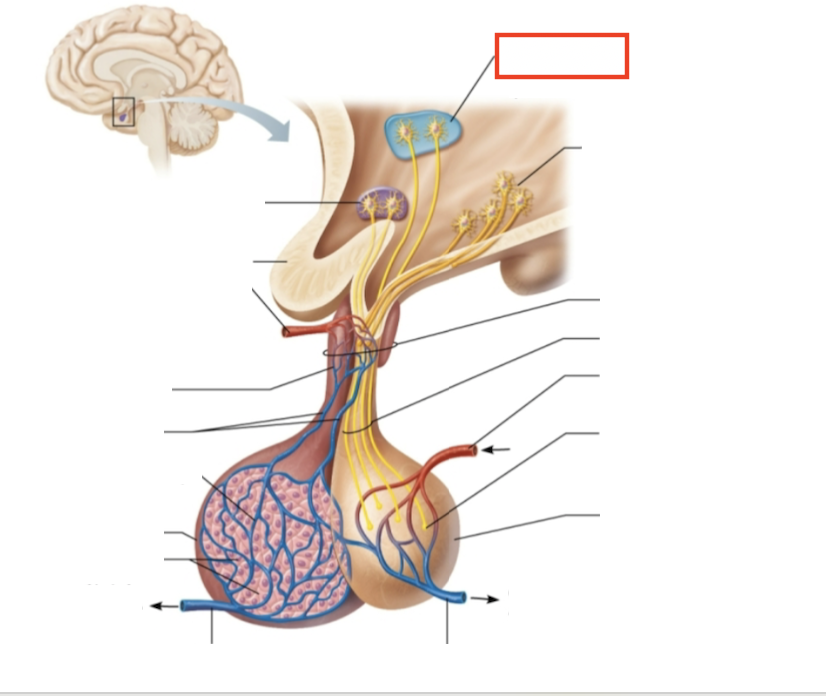

What structure is highlighted?

hypothalamic neurons in the paraventricular nuclei

What structure is highlighted?

neurons in the ventral hypothalamus

What structure is highlighted?

infundibulum (connecting stalk)

What structure is highlighted?

hypothalamic-hypophyseal tract

What structure is highlighted?

inferior hypophyseal artery

What structure is highlighted?

neurohypophysis (storage area for hypothalamic hormones)

What structure is highlighted?

posterior pituitary

What molecules are produced here?

oxytocin, ADH

What structure is highlighted?

venule

What structure is highlighted?

venule

What molecules are produced here?

TSH, FSH, LH, ACTH, GH, PRL

What structure is highlighted?

secretory cells of adenohypophysis

What structure is highlighted?

anterior pituitary

What structure is highlighted?

secondary capillary plexus

What structure is highlighted?

hypophyseal portal veins

What structure is highlighted?

primary capillary plexus

What structure is highlighted?

superior hypophyseal artery

What structure is highlighted?

superior hypophyseal artery

What structure is highlighted?

optic chiasma

What structure is highlighted?

hypothalamic neurons in the supraoptic nuclei